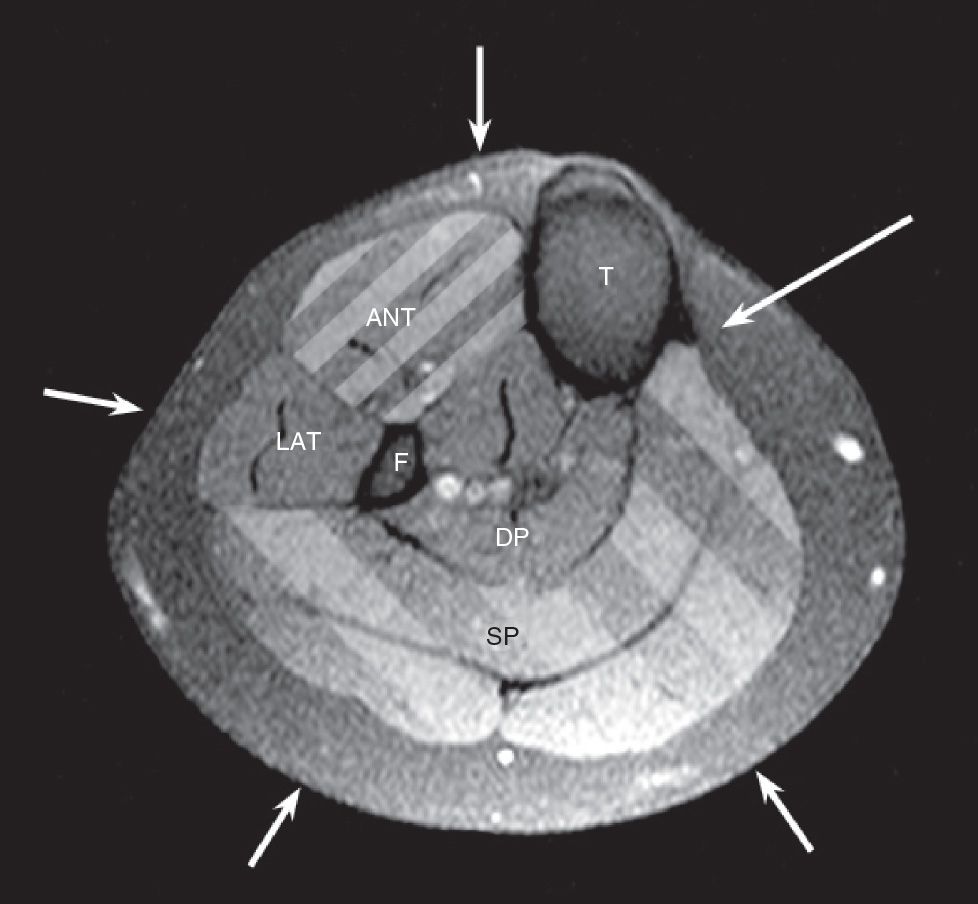

Figure 1 from Deep Posterior Compartment Pressure in the Evaluation of

Figure 1 from Compartment Pressure Curves Predict Surgical in Deep Posterior Compartment Pressure With the patient supine, elevate the leg slightly, if possible. The pain usually comes on during a run and goes away with rest, only to return when training resumes. The stryker ® system, a commercially available instrument, is used here. The fascia should be opened with partially opened scissors from the tibial tuberosity to the medial malleolus to effectively. Compartment. Deep Posterior Compartment Pressure.